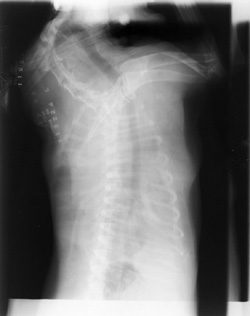

Double Exposures